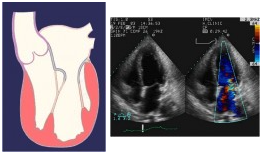

Insufficienza mitralica di tipo I, dovuta a dilatazione anulare e relativa immagine all’eco-colordoppler